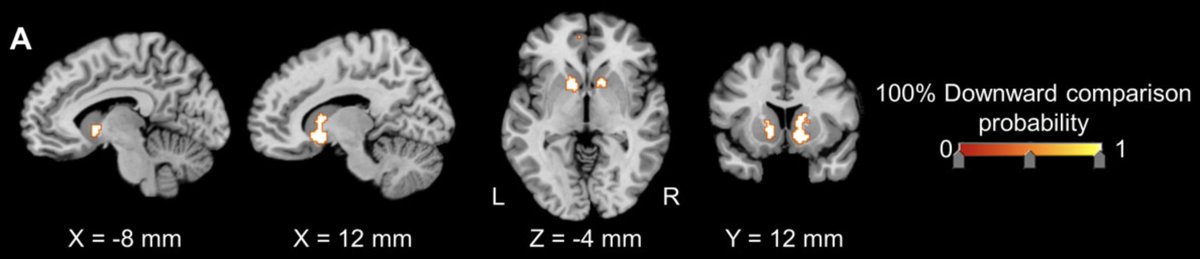

It's a joy when others are worse off than myself Social downward comparison robustly results in activation of the ventral striatum, a key brain region for reward processing https://onlinelibrary.wiley.com/doi/full/10.1002/hbm.23854 …pic.twitter.com/ywCp3kuyFD